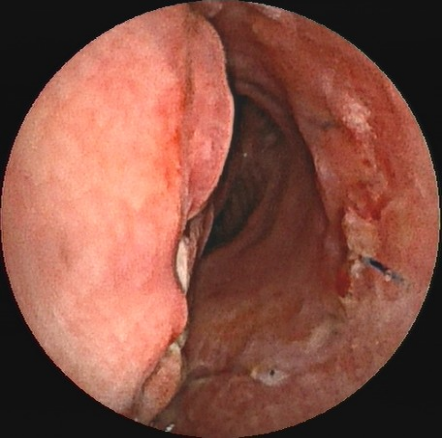

患者支架置入术前气管管壁严重塌陷、管腔狭窄

气道内支架置入术后狭窄气道重新开放